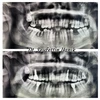

الدكتور سيف الدين يانيك، يقدم خدمات صحية لمرضاه في تخصص طب الأسنان في مستشفى Cevizlibağ Hospitadent لصحة الفم والأسنان.

الدكتور سيف الدين يانيك، الذي تشمل مجالات اهتمامه جراحة الزراعة وتصميم الابتسامة الجمالية، شارك في العديد من المؤتمرات والدورات والندوات داخل البلاد.

طبيب أسنان